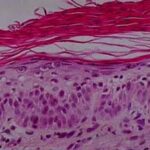

This variety of keratosis, sometimes referred to as florid keratosis, may easily be overdiagnosed as invasive squamous cell carcinoma by the unwary. Mild or moderate papillomatosis may be present. The epidermis is thickened in most areas and shows irregular downward proliferation that is limited to the uppermost dermis and does not represent frank invasion .A varying proportion of the keratinocytes in the stratum malpighii show a loss of polarity and thus a disorderly arrangement. Some of these cells show pleomorphism and atypicality (“anaplasia”) of their nuclei, which appear large, irregular, and hyperchromatic. Often the nuclei in the basal layer are closely crowded together. Some of the cells in the midportion of the epidermis show premature keratinization, resulting in dyskeratotic cells or apoptotic bodies characterized by homogeneous, eosinophilic cytoplasm with or without a nucleus. In contrast to the epidermal keratinocytes, the cells of the hair follicles and eccrine ducts that penetrate the epidermis within actinic keratoses retain their normal appearance and keratinize normally. Occasionally, cells of the normal adnexal epithelium extend over the atypical cells of the epidermis in an umbrella-like fashion. In some cases, abnormal keratinocytes extend downward on the outside of the follicular infundibulum to the level of the sebaceous duct and, less commonly, along the eccrine duct . |

In the atrophic type of actinic keratosis, hyperkeratosis usually is slight. The epidermis is thinned and devoid of rete ridges. Atypicality of the cells is found predominantly in the basal cell layer, which consists of cells with large hyperchromatic nuclei that lie close together. The atypical basal layer may proliferate into the dermis as buds and ductlike structures. It may also surround as cell mantles the upper portion of pilosebaceous follicles and sweat ducts, the epithelium of which otherwise appears normal . |